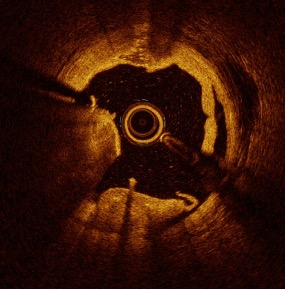

Examples of Calcium Fractures Visualized with OCT3

Concentric Calcified Lesion

Lesion with Calcified Nodule

Of the study population, 32 patients had additional OCT analysis. The study confirmed the mechanism of action, identifying deep calcium fractures in both eccentric and concentric calcified lesions.

of lesions with calcium fracture visible on OCT imaging

of lesions had multiple fractures